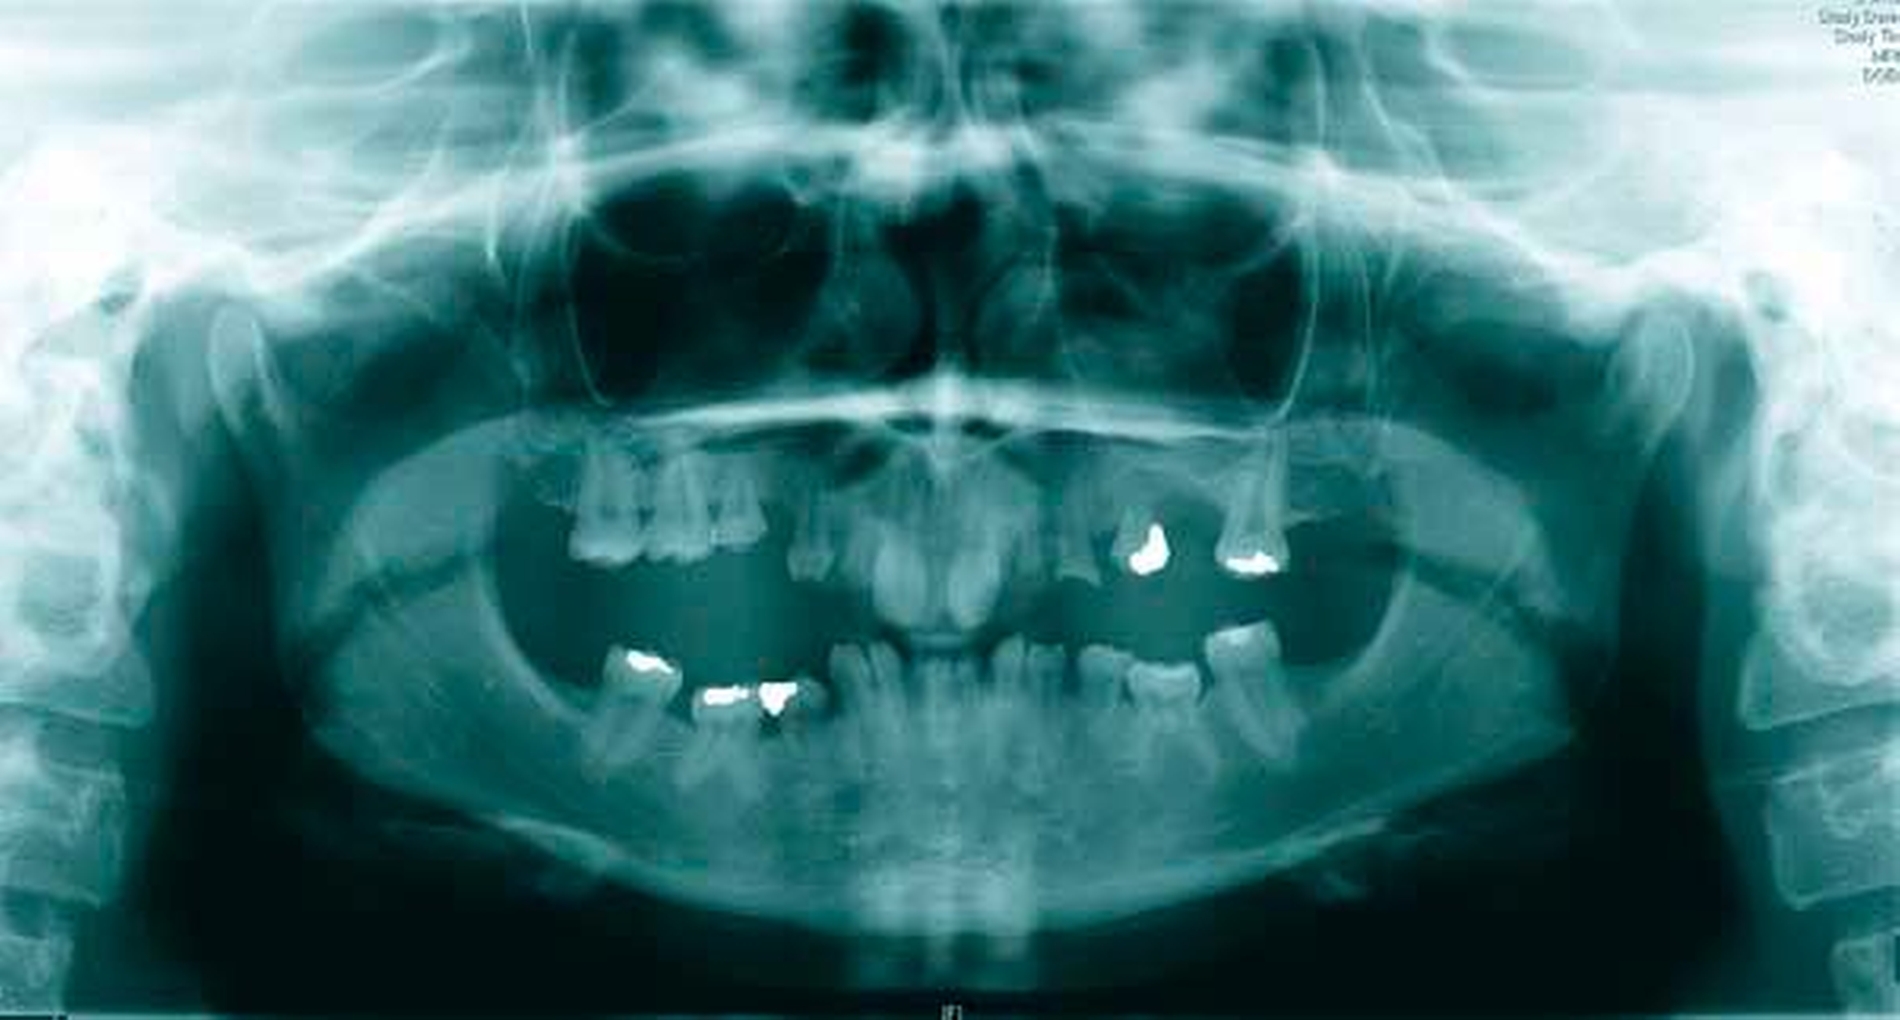

Ein 17-jähriger Patient wurde mit einer odontogenen Zyste im rechten Oberkiefer überwiesen (Abbildung 1). Bereits fünf Jahre zuvor waren bei ihm multiple Keratozysten entfernt und der Verdacht auf ein Gorlin-Goltz-Syndrom geäußert worden, dieser wurde jedoch nicht weiter abgeklärt. Anamnestisch lagen bisher keine Basalzellkarzinome vor.

Zur weiteren Beurteilung der Ausdehnung des Befunds wurde eine Nasennebenhöhlenaufnahme veranlasst (Abbildung 2). Darin zeigte sich eine deutlich sichtbare Verkalkung der Falx cerebri, was den klinischen Verdacht eines Gorlin-Goltz-Syndroms nach den Evans-Kriterien (Tabelle 1) [Evans et al.] bestätigte. Ein weiteres auffälliges Merkmal: ein vergrößerter Augenabstand (Hypertelorismus). Weitere, angeborene Fehlbildungen lagen nicht vor, die Familienanamnese war negativ.